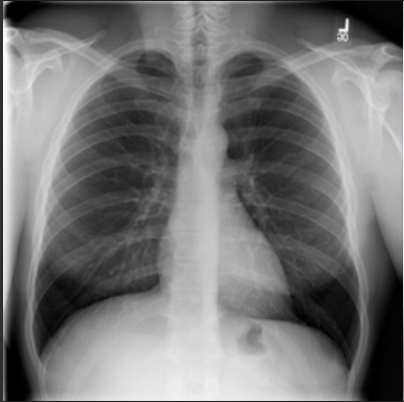

4.1 Qualitative Evaluation of Healthy Counterpart Generation

Example images from the disease COVID-19 Radiography Database and their generative healthy counterparts are given in figure 2. The images on the far left are instances of the lung opacity class from the real images in the dataset. The images in the middle column are examples of the generated healthy counterfactuals obtained via latent space diffusion, with RadBERT-guided textual-conditioning via a conditional prompt “normal chest x-ray”. A total of 75 diffusion inference steps are used with image conditioning strength=0.85 and guidance scale=7.5. (The former indicates the level of constraint on changes to the original input image and the latter is the weight given to the textual encoder conditioning in the generation of the image, ranging over [0,1] and [0,9], respectively).

Side-by-side inspection of the generated healthy counterfactuals (as per fig. 2) suggests that, as required, only minimal perturbation is made to the original image with respect to healthy pixels -i.e. localized image sites without structural medical defects. (In the top row, the medical structural defect in the original image is due to a lung opacity, and characterized via a relatively complex interaction between the imaging modality and subject manifesting as ‘gaps’ in the corresponding portions of the lung scan). The healthy/non-healthy discrepancy maps in all of these cases are obtained via masked subtraction of the original image from the generated image (the ground truth segmentation masks correspond to the broad area of interest –i.e. the complete lung). The generated healthy tissue is thus a subset of the mask and is shown in the final column of fig. 2 for the respective cases.

In the context of a VANT-GAN[20]-based approach, this highlighted material constitutes the diagnostic counterfactual visual attribution, i.e. the selection of material relevant to the diagnosis of the unhealthy condition. Healthy counterfactual generation was performed for the complete datasets in the three unhealthy classes, i.e Lung opacity, Viral Pneumonia and COVID, examples of which are given in fig. 3 for the three classes (all of the generated healthy counterfactuals from this experiment can be found on https://huggingface.co/ammaradeel/diffusionVA). Visual inspection indicates that the generated counterfactuals are, in general, visually plausible with minimal perturbation made to the unhealthy image overall. Moreover, the healthy counterpart generation does not appear to unnecessarily affect aspects of the images unrelated to the medical condition, the model selectively making changes to the unhealthy regions in a structurally plausible manner, e.g. generating missing portions of the lung without generating extraneous lung material where it would be expected to normally exist (e.g. in the abdominal cavity).